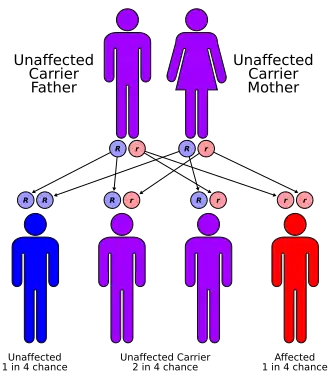

The hereditary ataxias are categorized by mode of inheritance and causative gene or chromosomal locus. The hereditary ataxias can be inherited in an autosomal dominant, autosomal recessive, or X-linked manner.

- There are five typical autosomal-recessive disorders in which ataxia is a prominent feature: Friedreich ataxia, ataxia-telangiectasia, ataxia with vitamin E deficiency, ataxia with oculomotor apraxia (AOA), spastic ataxia. Disorder subdivisions: Friedreich's ataxia, spinocerebellar ataxia, ataxia telangiectasia, vasomotor ataxia, vestibulocerebellar, ataxiadynamia, ataxiophemia, and olivopontocerebellar atrophy.

There are five typical autosomal recessive disorders in which ataxia is a prominent feature

There are five typical autosomal recessive disorders in which ataxia is a prominent feature